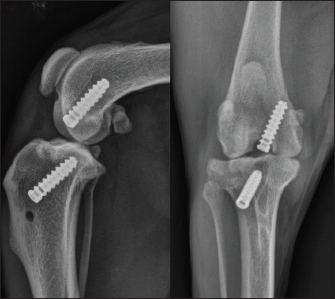

On day 1 post-surgery, the dog was walking on her operated leg with moderate lameness. During each postoperative consultation, two x-rays were performed (face and profile), as well as an orthopedic examination. A LOAD questionnaire was also completed. After 2 weeks, moderate lameness was observed, and radiographs showed thickening of the patellar tendon and moderate synovial inflammation; the LOAD score was 21/52. After 1 month, moderate lameness was persistent, radiographs still showed thickening of the patellar tendon and moderate synovial inflammation; the LOAD score was 13/52. After 2 months, moderate lameness was still observed, radiographs had not evolved, and the LOAD score was 7/52. After 3 months, mild lameness was observed, a mild posterior drawer was reported at orthopedic examination and moderate synovial inflammation was observed on radiographs (Fig. 6); the LOAD score was 7/52. After 6 months, very mild lameness was observed, a mild posterior drawer was reported at orthopedic examination and a resolution of the synovial inflammation was seen on radiographs (Fig. 7); the LOAD score was 5/52. After a year, a persistent yet stable mild posterior drawer was reported at the orthopedic examination but was not associated with any lameness, and the LOAD score was down to 2/52.

Fig. 7. 6-month postoperative radiographic views of dog's right pelvic limb from side (left) and front (right).